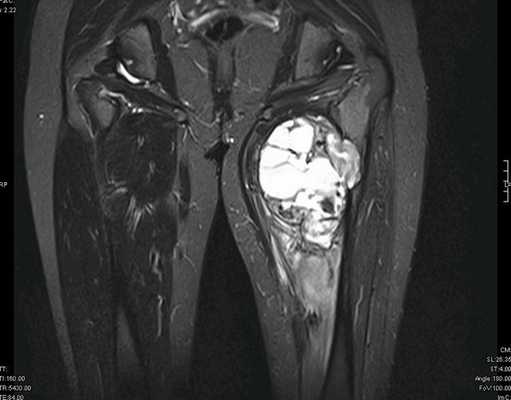

— МРТ первичной опухоли

Рисунок №2. Саркома мягких тканей верхней трети левого бедра